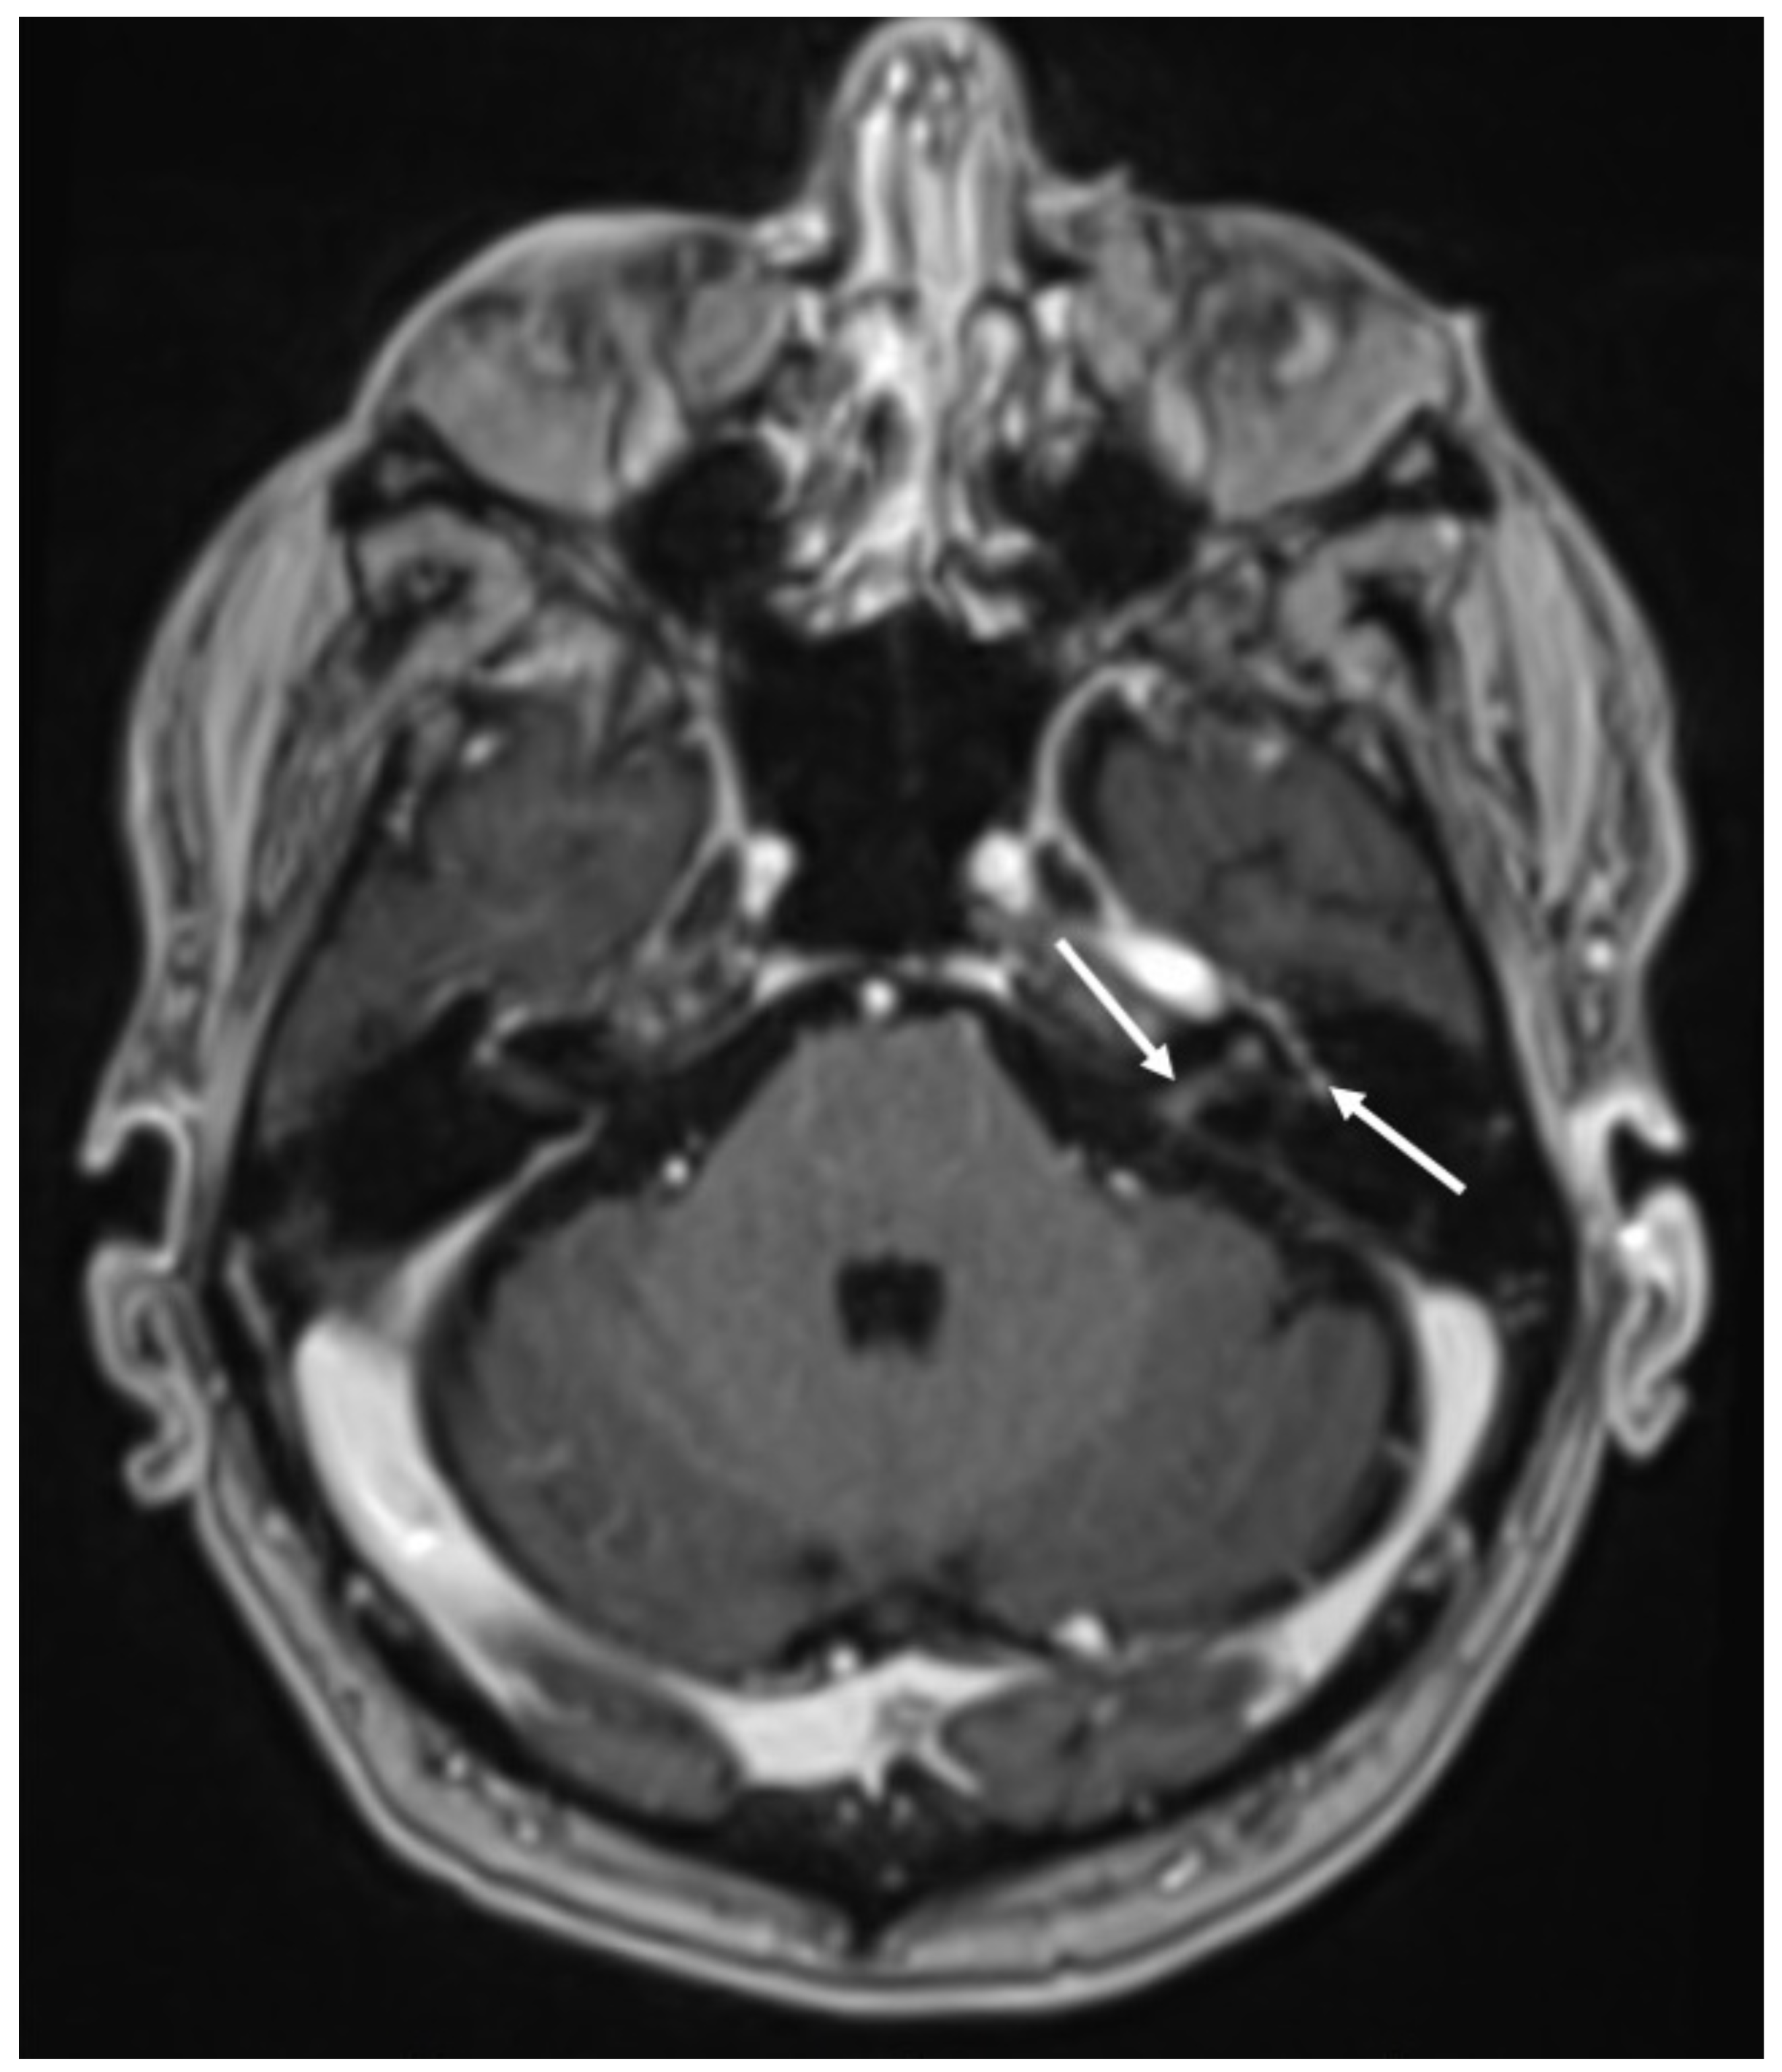

| Tuberculosis | • Leptomeningeal enhancement in the basal cisterns • Hydrocephalus very common • Infarcts in the basal ganglia due to vasculitis • Possible concomitant tuberculomas or miliary tuberculosis |

3. Tuberculous Meningitis/Meningoencephalitis